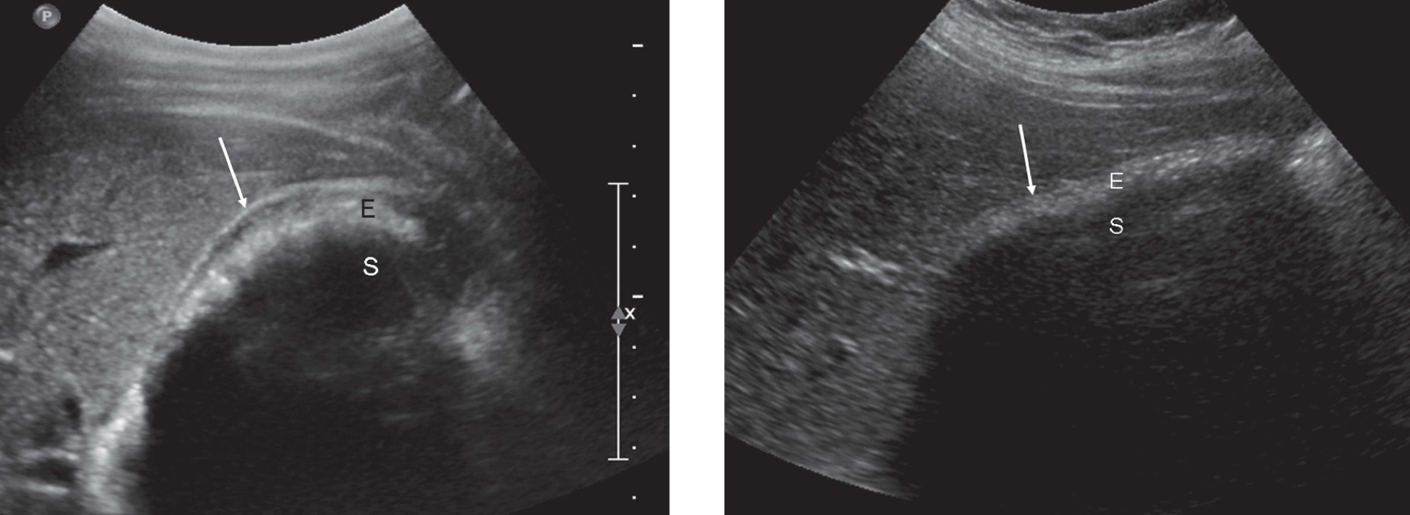

what is the Double Barrel Shotgun Sign?

dilated common bile duct

Portal Vein and Bile Duct near the same size due to dilation of the Bile Duct

See parallel tubular structures in the portal triad with two tubes about the same size.

what is shown?

double barrel shotgun sign